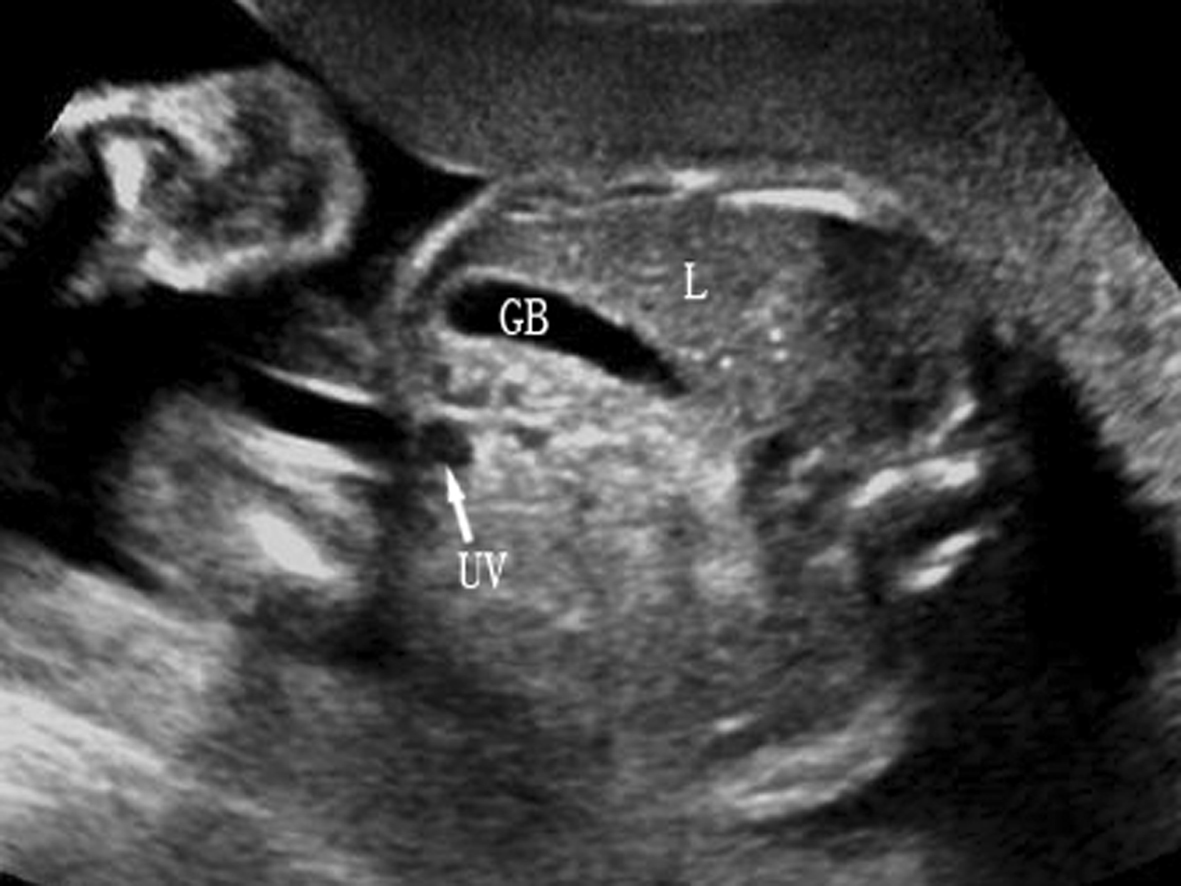

2.胆囊 14~16孕周后胎儿可显示胎儿胆囊回声(图2,GB)。正常胆囊长轴呈梨形,横切面呈类圆形,位于上腹部脐静脉(UV)腹腔段右侧,与脐静脉成一锐角,近腹壁但与腹壁不相连,无搏动,囊壁回声较脐静脉的管壁回声强,也较厚。当难以分辨胆囊与脐静脉时,可应用彩色多普勒超声进行鉴别。产前超声检查有时可显示胆囊结石、胆囊增大、胆囊水肿等,有报告染色体异常可能合并胆囊回声异常。

图2胎儿胆囊横切面声像图